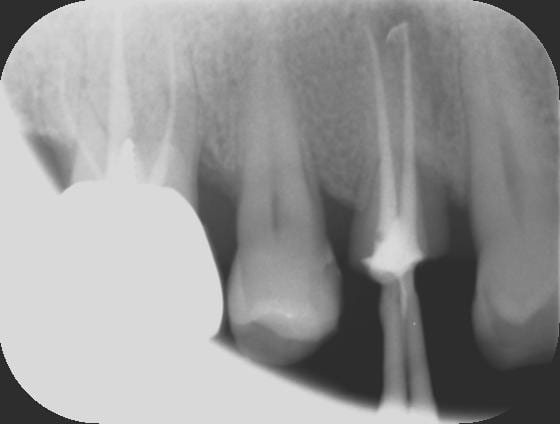

RTE avec le réciproc, c'est vraiment trop simple.